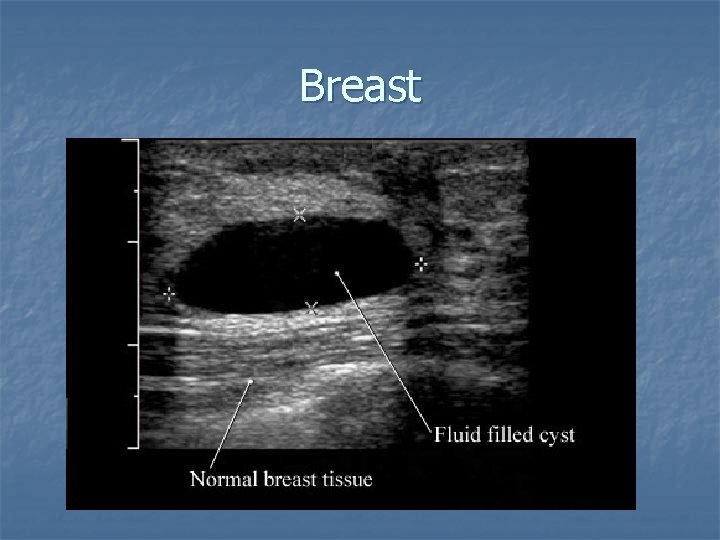

Breast